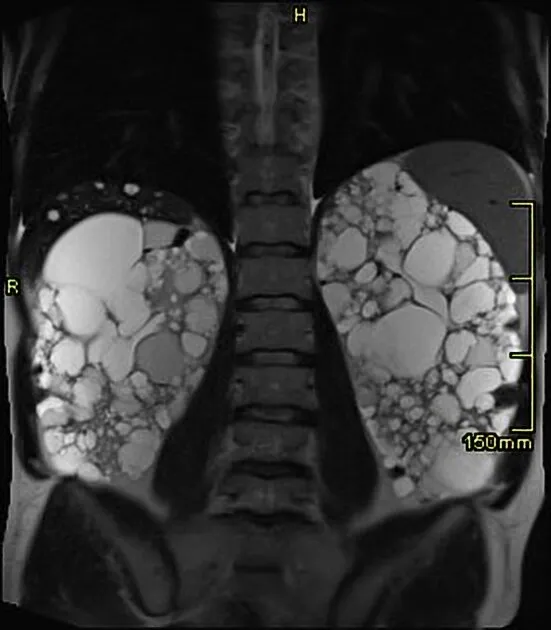

A DRPAD não é contraindicação à DP — e, na prática, muitos pacientes têm resultados comparáveis à hemodiálise. O “porém” está na mecânica: rins/hepatomegalia podem reduzir tolerância a volumes, aumentar risco de hérnias e extravasamentos, e piorar desconforto respiratório. Com técnica adequada (cateter presternal ou lateral, volumes menores, cicladora noturna e decúbito supino), a maioria das barreiras é contornável. Neste post, revisamos quando a DP é ótima, quando exigir cautela e como ajustar a prescrição para segurança e qualidade de vida.